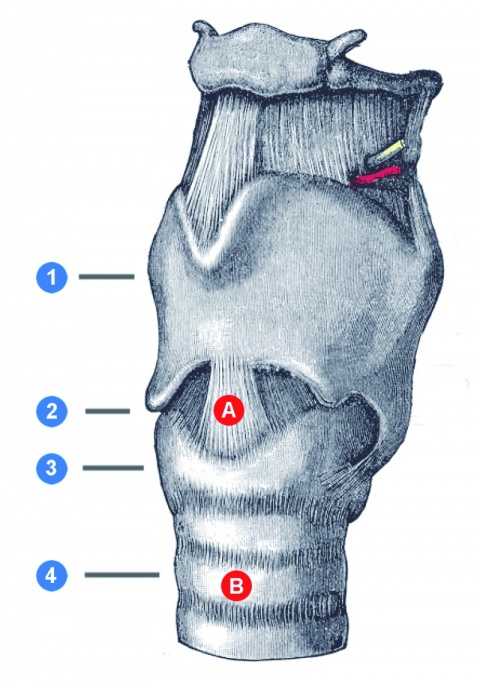

Fallbeispiel: Enchondrom

Zur Risikoklassifizierung von gutartigen Knochentumoren für die Beurteilung der allgemeinen Dienst- und Verwendungsfähigkeit von Soldaten Kevin Dallacker-Losensky¹, Magnus Scheer², Inken Seelmann¹, Michael Uhl³ ¹Sanitätsversorgungszentrum Volkach…